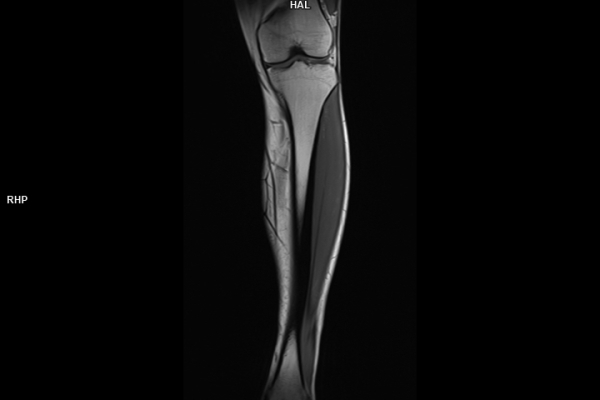

Detailbild MRT

Modernste Bildgebung für jeden Bereich Ihres Körpers

Entdecken Sie, welche CT- und MRT-Untersuchungen in unserer Radiologie für jeden Bereich Ihres Körpers möglich sind.

Die MRT (Magnetresonanztomographie) arbeitet mit Magnetfeldern und Radiowellen und eignet sich besonders für Untersuchungen der Weichteile wie Gehirn, Muskeln oder Gelenke. Die CT (Computertomographie) nutzt Röntgenstrahlen und liefert schnelle, hochauflösende Bilder, insbesondere für Knochen, Lunge oder innere Organe. Die Wahl der jeweiligen Untersuchung richtet sich an das individuelle Krankheitsbild und wird bei der Überweisung festgelegt.